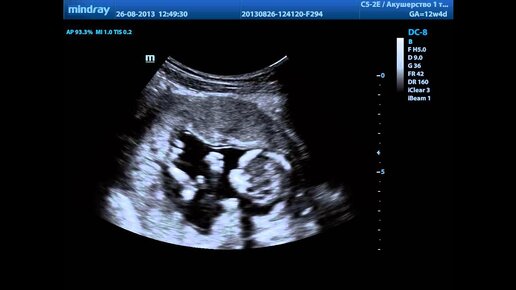

Продолжительность первого триместра беременности составляет 12 недель, за этот период у плода сформируются все основные системы и органы. К сожалению, в этот период происходит наибольшее количество осложнений, поэтому нужно быть внимательной к себе и своему организму. Будущей маме необходимо в первый триместр беременности больше отдыхать, не перетруждаться на работе, избегать стрессов и конфликтных ситуаций. Читайте подробнее о состоянии женщины в этот период: Беременность по триместрам: состояние...